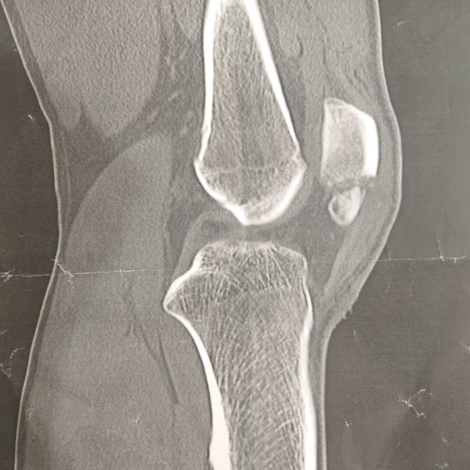

Dec 22, 15 · POINT 膝蓋骨骨折とは 膝蓋骨は一般的に「膝の皿」と言われる部分のことです。 膝蓋骨は膝の動きを効率化して滑らかにする役割があります。 膝蓋骨が折れると、強い痛みや腫れ、動かしづらさなどが現れます。 レントゲン検査やCT検査といった画像検査によって診断が行われ、骨折の程度が調べられます。 骨折の状況から保存的治療(固定・安静・鎮痛)と手術膝のお皿を骨折した話2 手術までの日常編 2 mem 1349 ひざを骨折した日から、ガンダム(ニーブレース)を付けた日々が始まりました。転倒や交通事故などで膝のお皿を強打し、骨折する事を膝蓋骨骨折といいます。 膝蓋骨は人体最大の種子骨で、大腿四頭筋と膝蓋靱帯に包み込まれています。 膝関節の保護と膝を伸ばすのに重要な役割を果たしています。 膝関節に起こる骨折の中では1番多く、スポーツをする人や若者から高齢者まで、幅広い年齢層で起こります。 骨折の頻度としては、そこまで

膝蓋骨骨折(しつがいこつこっせつ)とは、膝蓋骨が骨折した状態のことである 。 症状は膝前面の痛み、腫れ、打撲が挙げられる 。 人によっては歩けなくなることもある 。 合併症には脛や大腿骨や膝靭帯の損傷が挙げられる 。 一般的な原因は膝前面の膝からの落下などによる強打によるものNov 08, 19 · 1膝のお皿を骨折! 手術はするの! ? 全治はどのくらい? スポンサーリンク 目次 ついにやってしまいました はじめは折れてると思っていなかった 骨折をした時の状況骨折日記 目次 1膝のお皿を骨折!手術はするの!?全治はどのくらい? 2膝蓋骨骨折手術は免れたが生活は不便?お役立ちグッズをご紹介! 3骨折後1週間順調に回復!スタスタ歩いています! 4膝のリハビリ間近。

膝蓋骨骨折 一般社団法人 日本骨折治療学会 骨折の解説